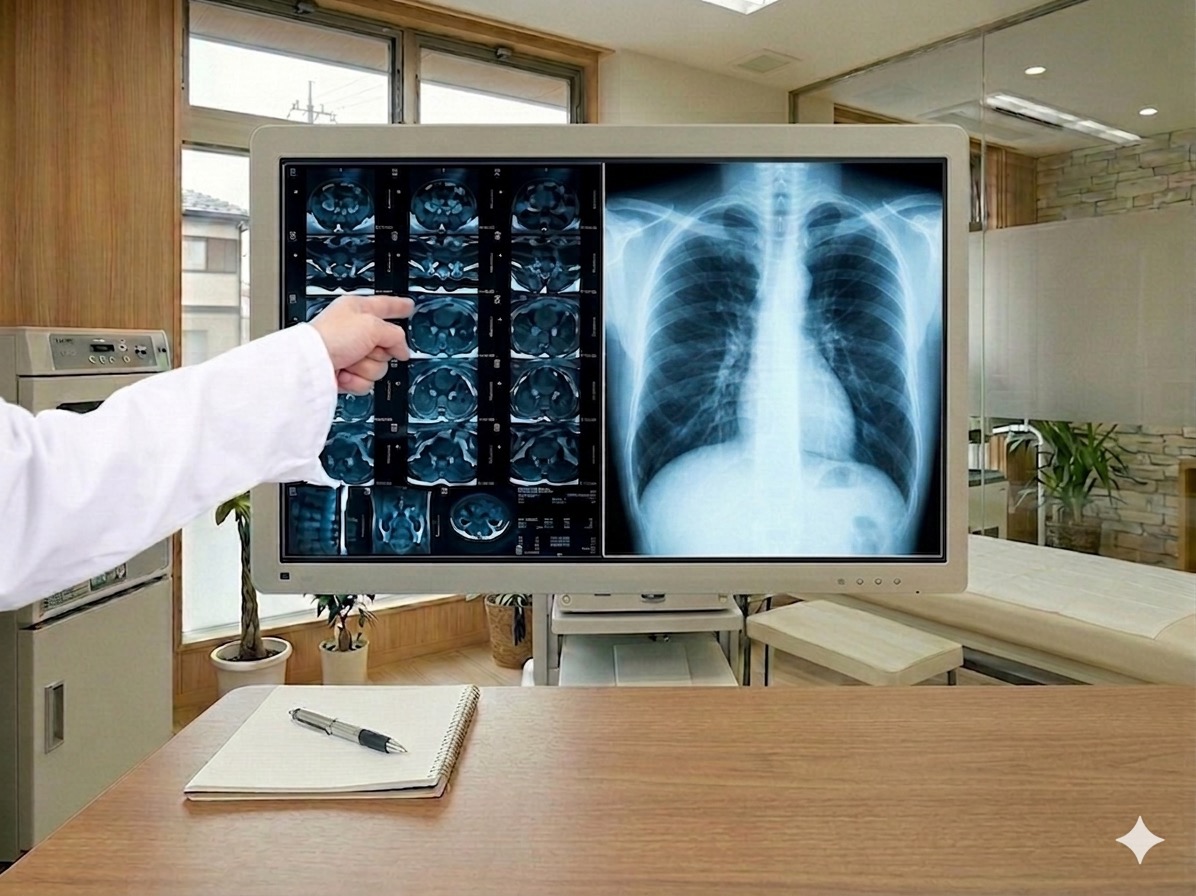

胸部や腹部のX線撮影を行います。肺炎や気胸の診断、腸閉塞や消化管穿孔の確認など、幅広い疾患のスクリーニングに使用します。撮影は数分で完了し、その場で結果をご説明いたします。

一般健康診断、雇入れ時健診、定期健康診断に対応しています。身体測定・血圧測定・血液検査・尿検査・心電図・レントゲンなど、各種検査をまとめて受けることができます。オプションで内視鏡検査の追加も可能です。